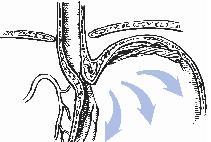

εικ.1

Σε φυσιολογικές συνθήκες υπάρχει ένας μηχανισμός που ενώ επιτρέπει την είσοδο της τροφής στο στομάχι, εμποδίζει την παλινδρόμηση γαστρικού περιεχομένου στον οισοφάγo (εικ.1).

Στον μηχανισμό αυτό που είναι γνωστός ως "αντιπαλινδρομικός φραγμός" συνεισφέρουν με την δράση τους διάφοροι ανατομικοί και λειτουργικοί παράγοντες: ο κατώτερος οισοφαγικός σφιγκτήρας, το μήκος του κοιλιακού τμήματος του οισοφάγου, οι ενδοκοιλιακές πιέσεις. Μεγαλύτερη συνεισφορά στον "αντιπαλινδρομικό φραγμό", σύμφωνα με τις πιό σύγχρονες μελέτες, έχει η γωνία με την οποία εισέρχεται ο οισοφάγος στο στομάχι (γωνία του Hiss), και η γαστρο-οισοφαγική βαλβίδα που δημιουργεί. Σε πολλούς ασθενείς που πάσχουν από ΓΟΠ, η βαλβίδα δεν λειτουργεί σωστά με αποτέλεσμα να μην μπορεί να αποτρέψει την παλινδρόμηση προς τον οισοφάγο. Ένας επιβαρυντικός παράγοντας είναι η παρουσία διαφραγματοκήλης, η μετακίνηση δηλαδή τμήματος του στομάχου από την κοιλιά στον θώρακα, η οποία επιδεινώνει την ανεπάρκεια της γαστρο-οισοφαγικής βαλβίδας αφού διαταράσσει την ανατομία της γαστροοισοφαγικής συμβολής.